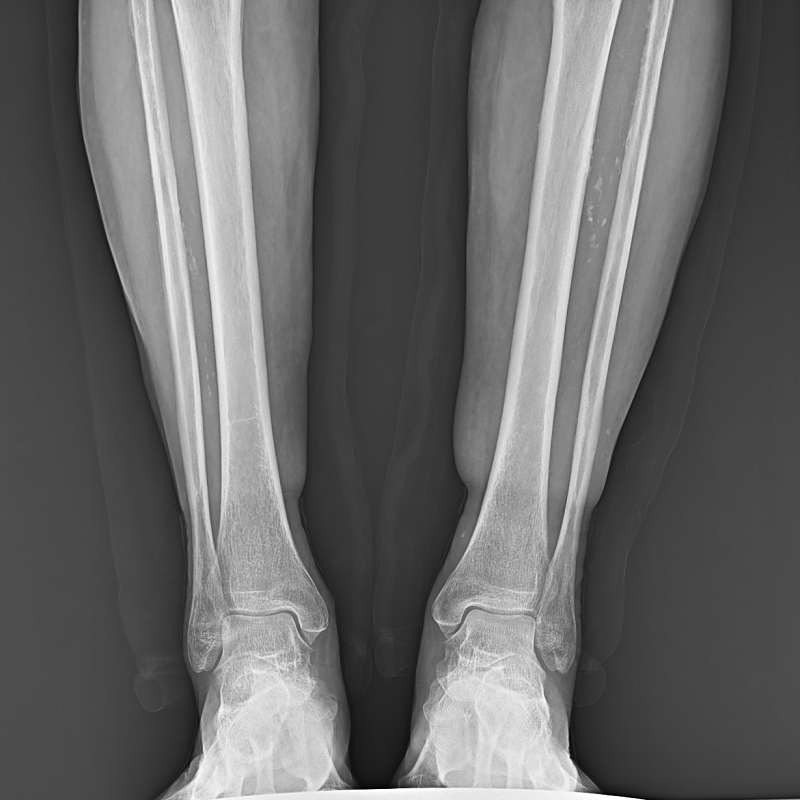

●呈現全下肢或全脊柱圖像

●在脊柱及下肢畸形矯正手術(shù)治療中,為術(shù)前方案制定和術(shù)后復查提供精準測量

●有效解決傳統X光片不能一次成像問(wèn)題,為患者提供更加優(yōu)質(zhì)的醫療服務(wù)

點(diǎn)片裝置可實(shí)現大范圍縱向移動(dòng),高效完成各部位、全身拼接等檢查需求